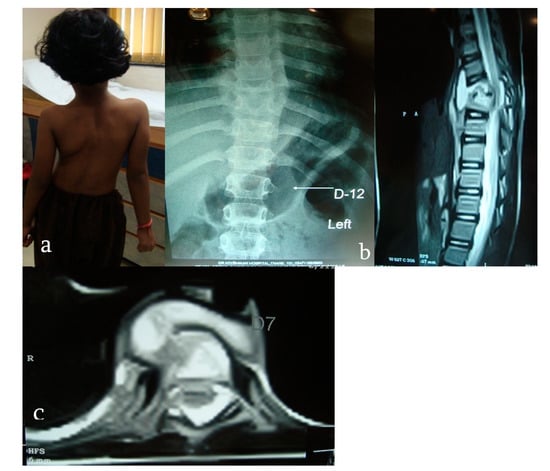

2.2. Imaging Features

- OA TB is paucibacterial, often slowly progressive, accompanied by constitutional symptoms in about one-third to one-half of cases. Spinal TB is the most common presentation of OA TB.